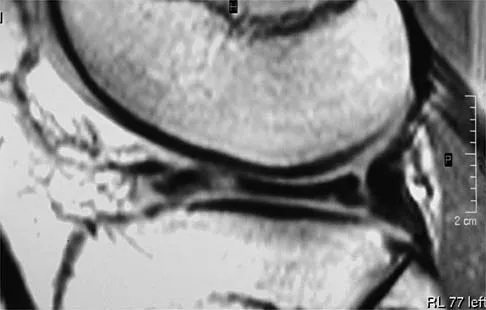

A 40-year-old woman has a symptomatic mass on the anterior aspect of the ankle. She reports no constitutional symptoms. An MRI scan is shown in Figure 12. What is the most likely diagnosis?